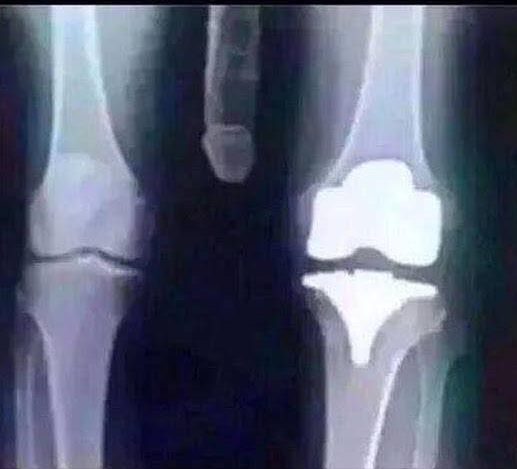

Hab hier mal ne Aufnahme von meinem Knie angehängt, der Arzt meint, alles gut, was meint der Fachmann?